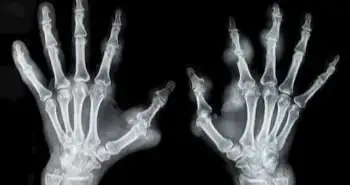

Are you at risk of developing rheumatoid arthritis?